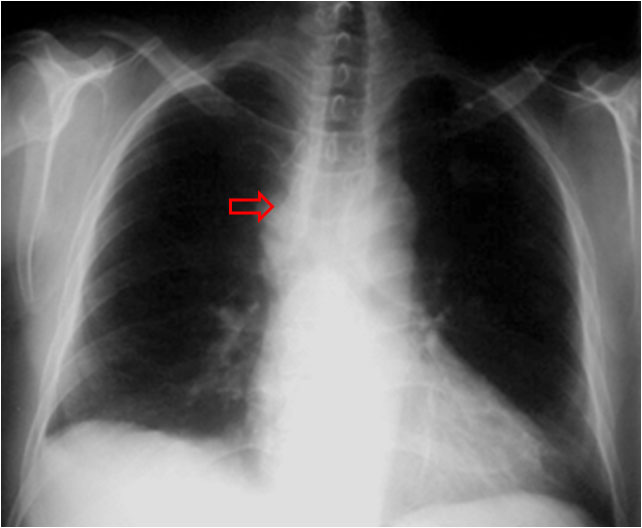

SIGNO DEL ENGROSAMIENTO DE LA LÍNEA PARATRAQUEAL DERECHA

La línea paratraqueal derecha es una línea de densidad agua que desciende entre el margen derecho de la luz traqueal y el pulmón derecho. En sujetos normales esta línea no debe superar los 4 mm. El ensanchamiento igual o superior a 5 mm es una evidencia inequívoca de patología. El diagnóstico diferencial incluye adenopatías, inflamación o hemorragia mediastínicas, engrosamiento o derrame pleural y patología traqueal.

En la radiografía se puede ver el engrosamiento de la línea paratraqueal derecha (flecha) que corresponde a una masa.

La TC muestra la masa mediastínica que ensancha el espacio paratraqueal derecho que justifica el signo (flechas). En este caso se trata de un conglomerado de adenopatías.